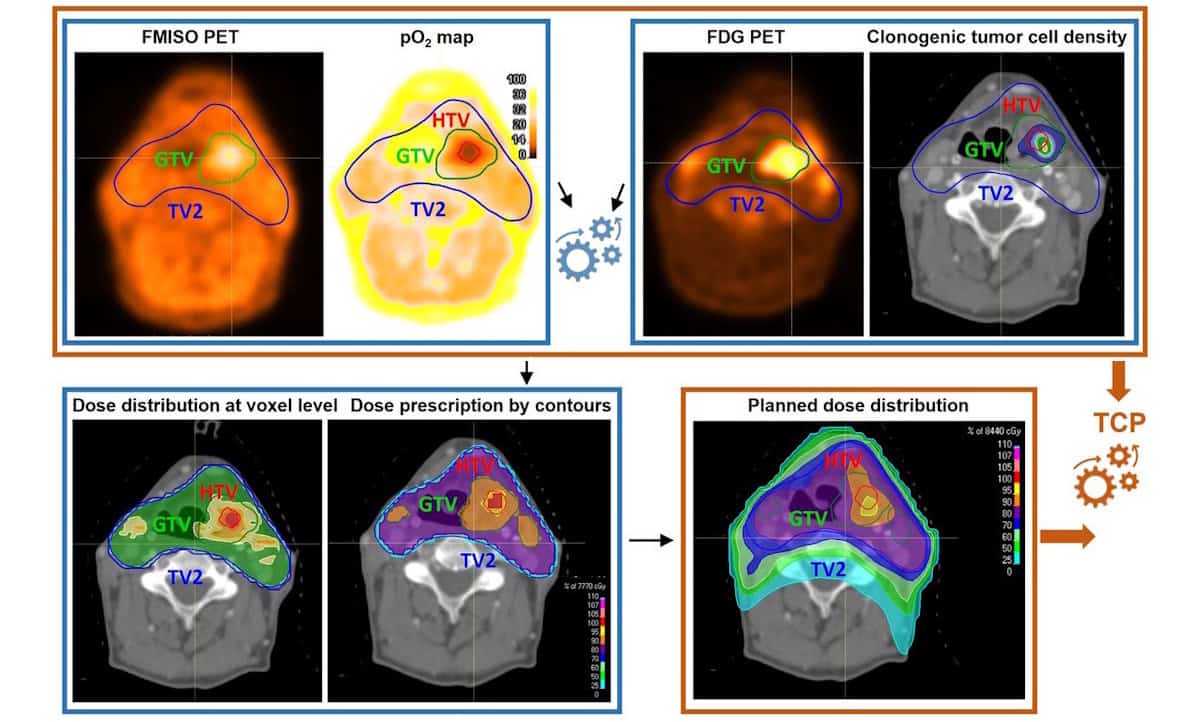

The research team, led by Marta Lazzeroni from Stockholm University, assessed 28 patients who underwent two pre-treatment PET/CT scans. These scans utilized two different tracers: 18 F-fluoromisonidazole (FMISO) to measure radioresistance and 18 F-FDG to evaluate tumor cellularity. This dual approach addresses the inherent radiosensitivity and heterogeneity of tumors, factors that significantly impact treatment outcomes.

Lazzeroni explained that “FMISO provides information on hypoxia-related radioresistance, but tumor control also strongly depends on the number of clonogenic cells, which is not captured by hypoxia imaging alone.” The study marks a pioneering effort to integrate both FMISO and FDG PET data within a unified framework to enhance dose escalation tailored to individual tumor profiles.

Using the data from the PET scans, the researchers created voxel-level maps to assess oxygen partial pressure (pO2) in the tumors, subsequently defining a hypoxic target volume (HTV). The FDG scans provided insight into the distribution of clonogenic tumor cell density, which directly influences the necessary dose to achieve a specific tumor control probability (TCP).

The automated planning system generated volumetric-modulated arc therapy plans that included 35 treatment fractions with an integrated boost for radioresistant subvolumes, while ensuring safe sparing of critical organs. Each treatment plan achieved an average biologically equivalent dose of 81±3.2 Gy to the HTV, successfully adhering to clinical safety standards for protecting the brainstem, spinal cord, and mandible. Notably, parotid glands were spared in 75% of cases.

The results indicate a significant advancement in the field, suggesting that the personalized dose-escalation strategy is clinically feasible and could be integrated into current treatment protocols. The research team also conducted a radiobiological evaluation, calculating TCP based on the planned dose distribution and PET-derived data. The findings revealed TCP values exceeding 90% for all patients, a substantial improvement compared to the typical 60% tumor control rates documented in existing clinical literature for HNSCC.